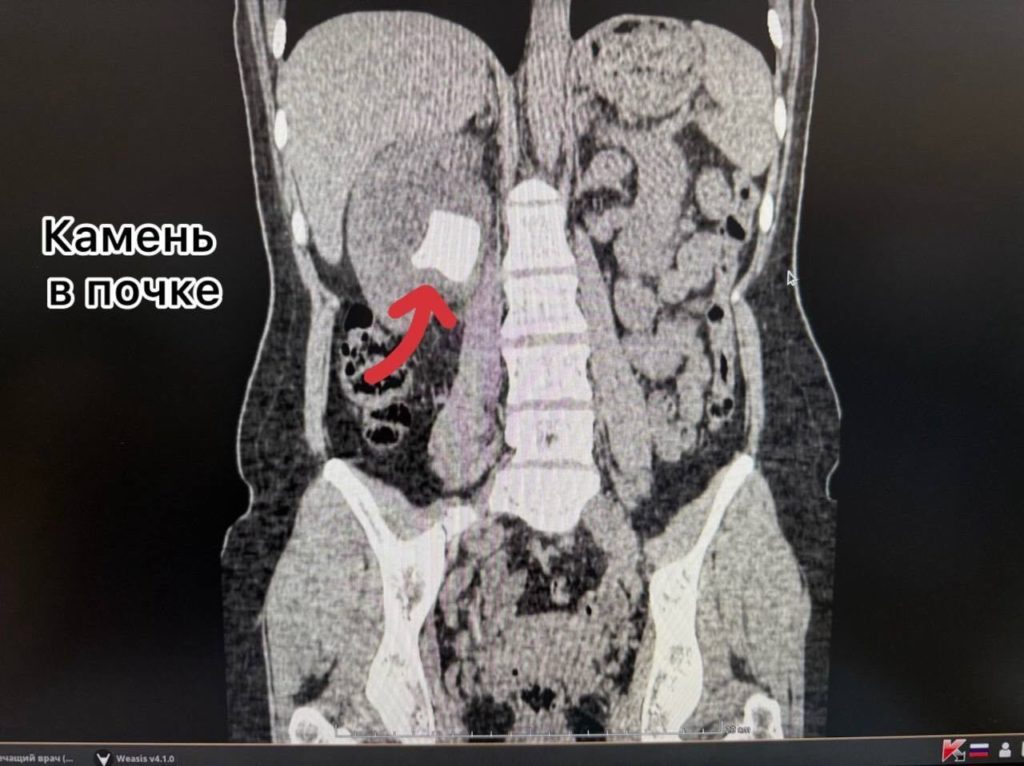

За это время на трубке образовались солевые отложения, сформировавшие крупные камни как в почке, так и в мочевом пузыре.

Помощь была оказана в приоритетном порядке по системе «зелёного коридора», так как пациентка является супругой участника СВО. Перед врачами стояла сложная трёхэтапная задача: удалить камень из почки, раздробить и извлечь камень из мочевого пузыря и убрать сам инкрустированный стент.

Урологи Александр Певчев и Мадина Абдуллаева провели уникальное сочетанное вмешательство за одну операцию. Через минимальный прокол в пояснице ультразвуком был разрушен почечный камень, а через естественные пути лазером раздроблены и удалены камень из мочевого пузыря и стент. Вся процедура выполнялась с эндоскопическим и рентгенологическим контролем.